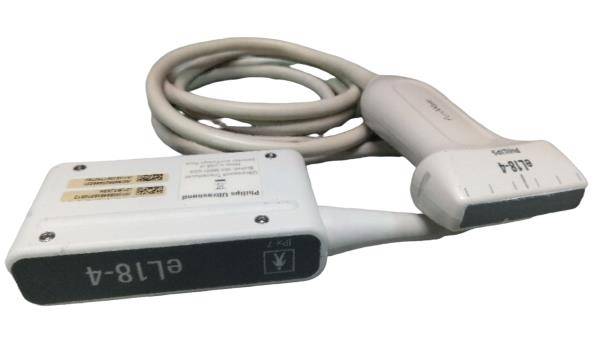

The Philips CX50 Portable Ultrasound System emerges as an exceptional choice for medical professionals seeking top-tier cardiac and vascular imaging capabilities. This seller refurbished unit has undergone rigorous inspection, cleaning, and restoration processes to ensure its return to peak working condition, almost indistinguishable from its original state, even if the original packaging may not be present.

With a special focus on cardiac echo and vascular diagnostics, this system includes a warranty that underscores our commitment to quality and customer satisfaction. The Philips CX50 is renowned for its stellar performance and reliability in various clinical settings.